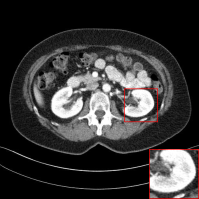

Figure 13: Qualitative results of our method and other baselines on Mayo Clinic Low Dose CT dataset. As shown in the highlighted red box, the reconstructed images by our method have few noise and preserve the details of organs. The display window is [160,240]160240[160,240] HU.

D.1 Low-Dose CT

In this subsection, we show the additional qualitative results on Low-Dose CT dataset authorized by Mayo Clinic [Moen etย al.(2021)Moen, Chen, Holmesย III, Duan, Yu, Yu, Leng, Fletcher, and McCollough] in Figure 13. As shown in Figure 13, previous methods tend to lose details and generate blurred results. However, our method removes the noise, while preserving the details of organs. It shows that our method is also practical for medical image denoising.